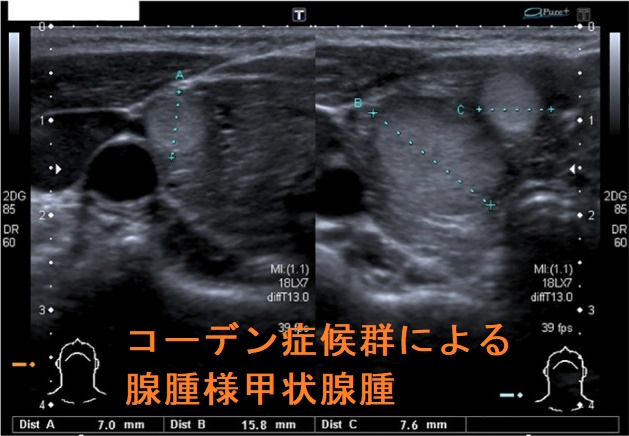

- 甲状腺良性結節(腺腫様甲状腺腫・良性濾胞腺腫)70%

腺腫様甲状腺腫・良性濾胞腺腫

コーデン(Cowden)症候群による腺腫様甲状腺腫を認めた場合、甲状腺分化癌(甲状腺乳頭癌・甲状腺濾胞癌)が発生する、あるいは既に合併している可能性があるため、甲状腺全摘出します。多発する腺腫様結節のいずれが、どの部分が癌化しているか事前に同定するのは困難で、しかも全ての甲状腺細胞がPTEN遺伝子変異を持っている限り、いつか、どれかが癌化する危険があります。